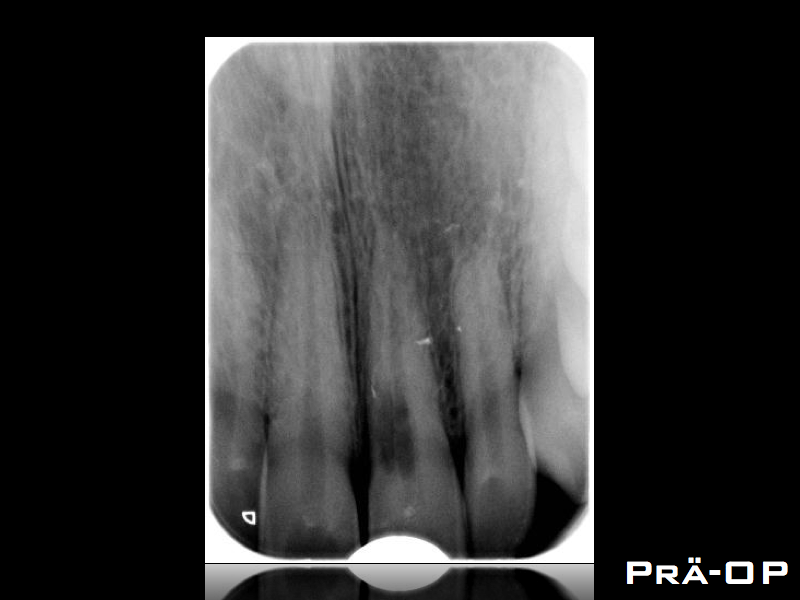

ECIR.001